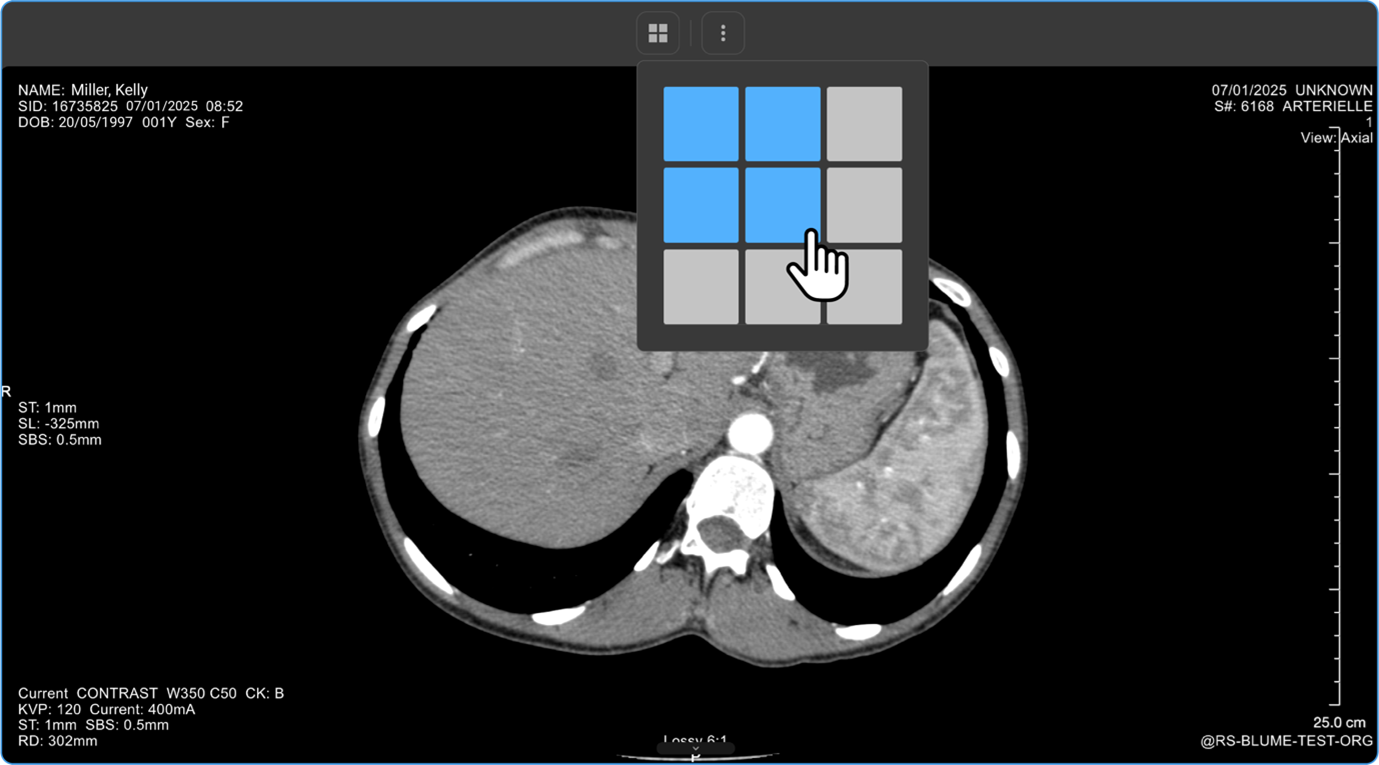

How Do I Change the Viewport Layout?

1. Open Layout Selector from the toolbar.

a. A 3×3 grid appears, with the current layout highlighted.

1. Adjust Viewports:

a. Drag to increase/decrease viewports (up to 8×8 grid per monitor).